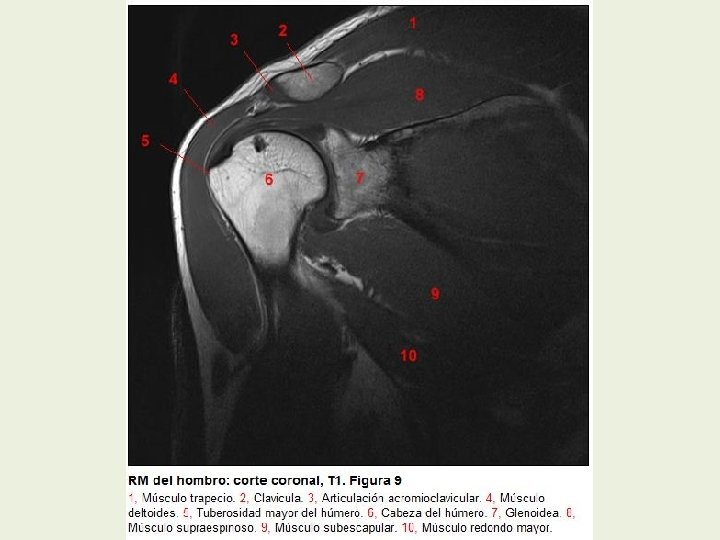

Hombro Cortes coronales RMN